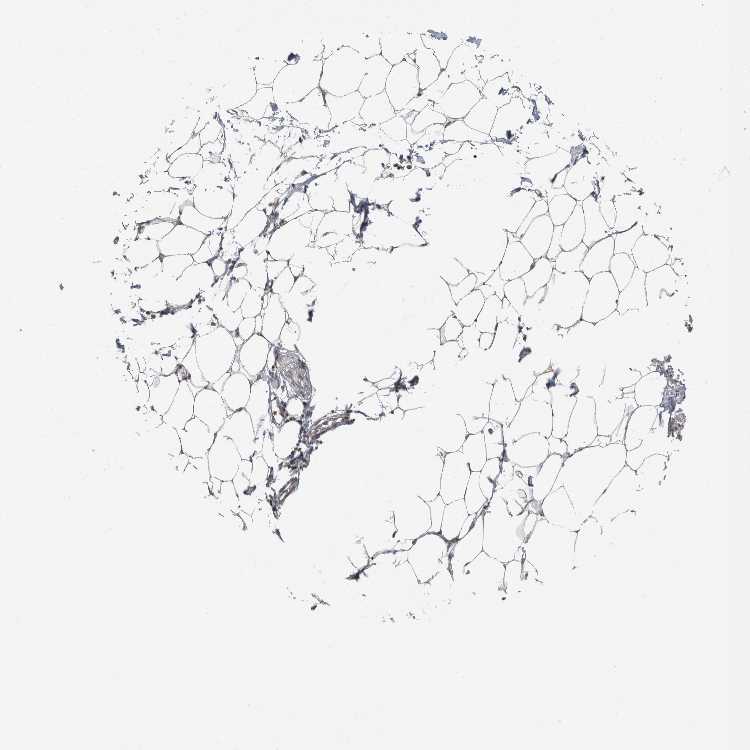

SOFT TISSUE 2 - Antibody stainingi

Antibody staining in the annotated cell types in the current human tissue is reported as not detected, low, medium, or high, based on conventional immunohistochemistry profiling in selected tissues. This score is based on the combination of the staining intensity and fraction of stained cells.

Each image is clickable and will lead to virtual microscopy that enables deeper exploration of all samples and also displays staining intensity scores, fraction scores and subcellular localization as well as patient and tissue information for each sample.

Antibody HPA020344Antibody HPA024149

Fibroblasts Not detectedNot detected

Peripheral nerve High-